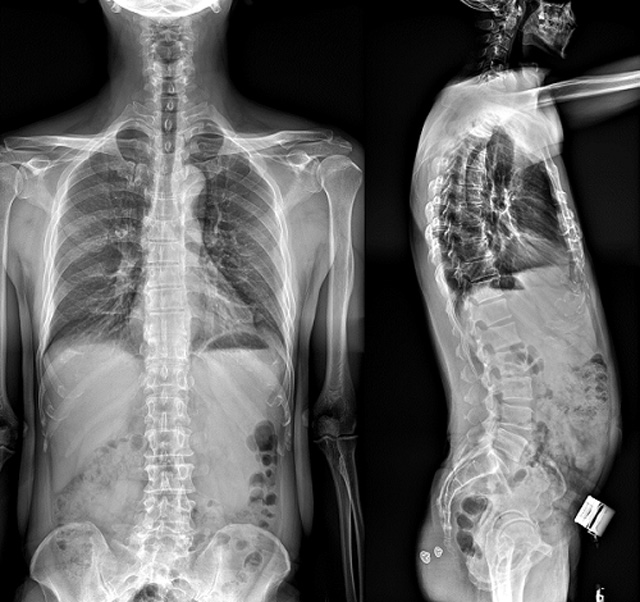

(7)全身拼接功能對有較大尺寸全脊柱拼接圖接桂成金下股分成幾次拍攝,再經(jīng)過秋件開在骨科開展的全脊柱畸形矯治工作中,雖然CT. MRI也能獲取全脊柱影像,接圖像,以便于長度、角度、力線等測量和察脊柱在重力情況下但不能進行立位檢查,無法觀全景觀察。全身拼接功能是高等級DR攝取患者立位全下的功能狀態(tài)圖像,因此采用動態(tài)醫(yī)院特別看重的動態(tài)DR功能之一。注:圖中Cobb脊柱正側(cè)位圖像是首選的檢查方法角度的大小是反映側(cè)彎嚴(yán)重程度的一個標(biāo)準(zhǔn)。